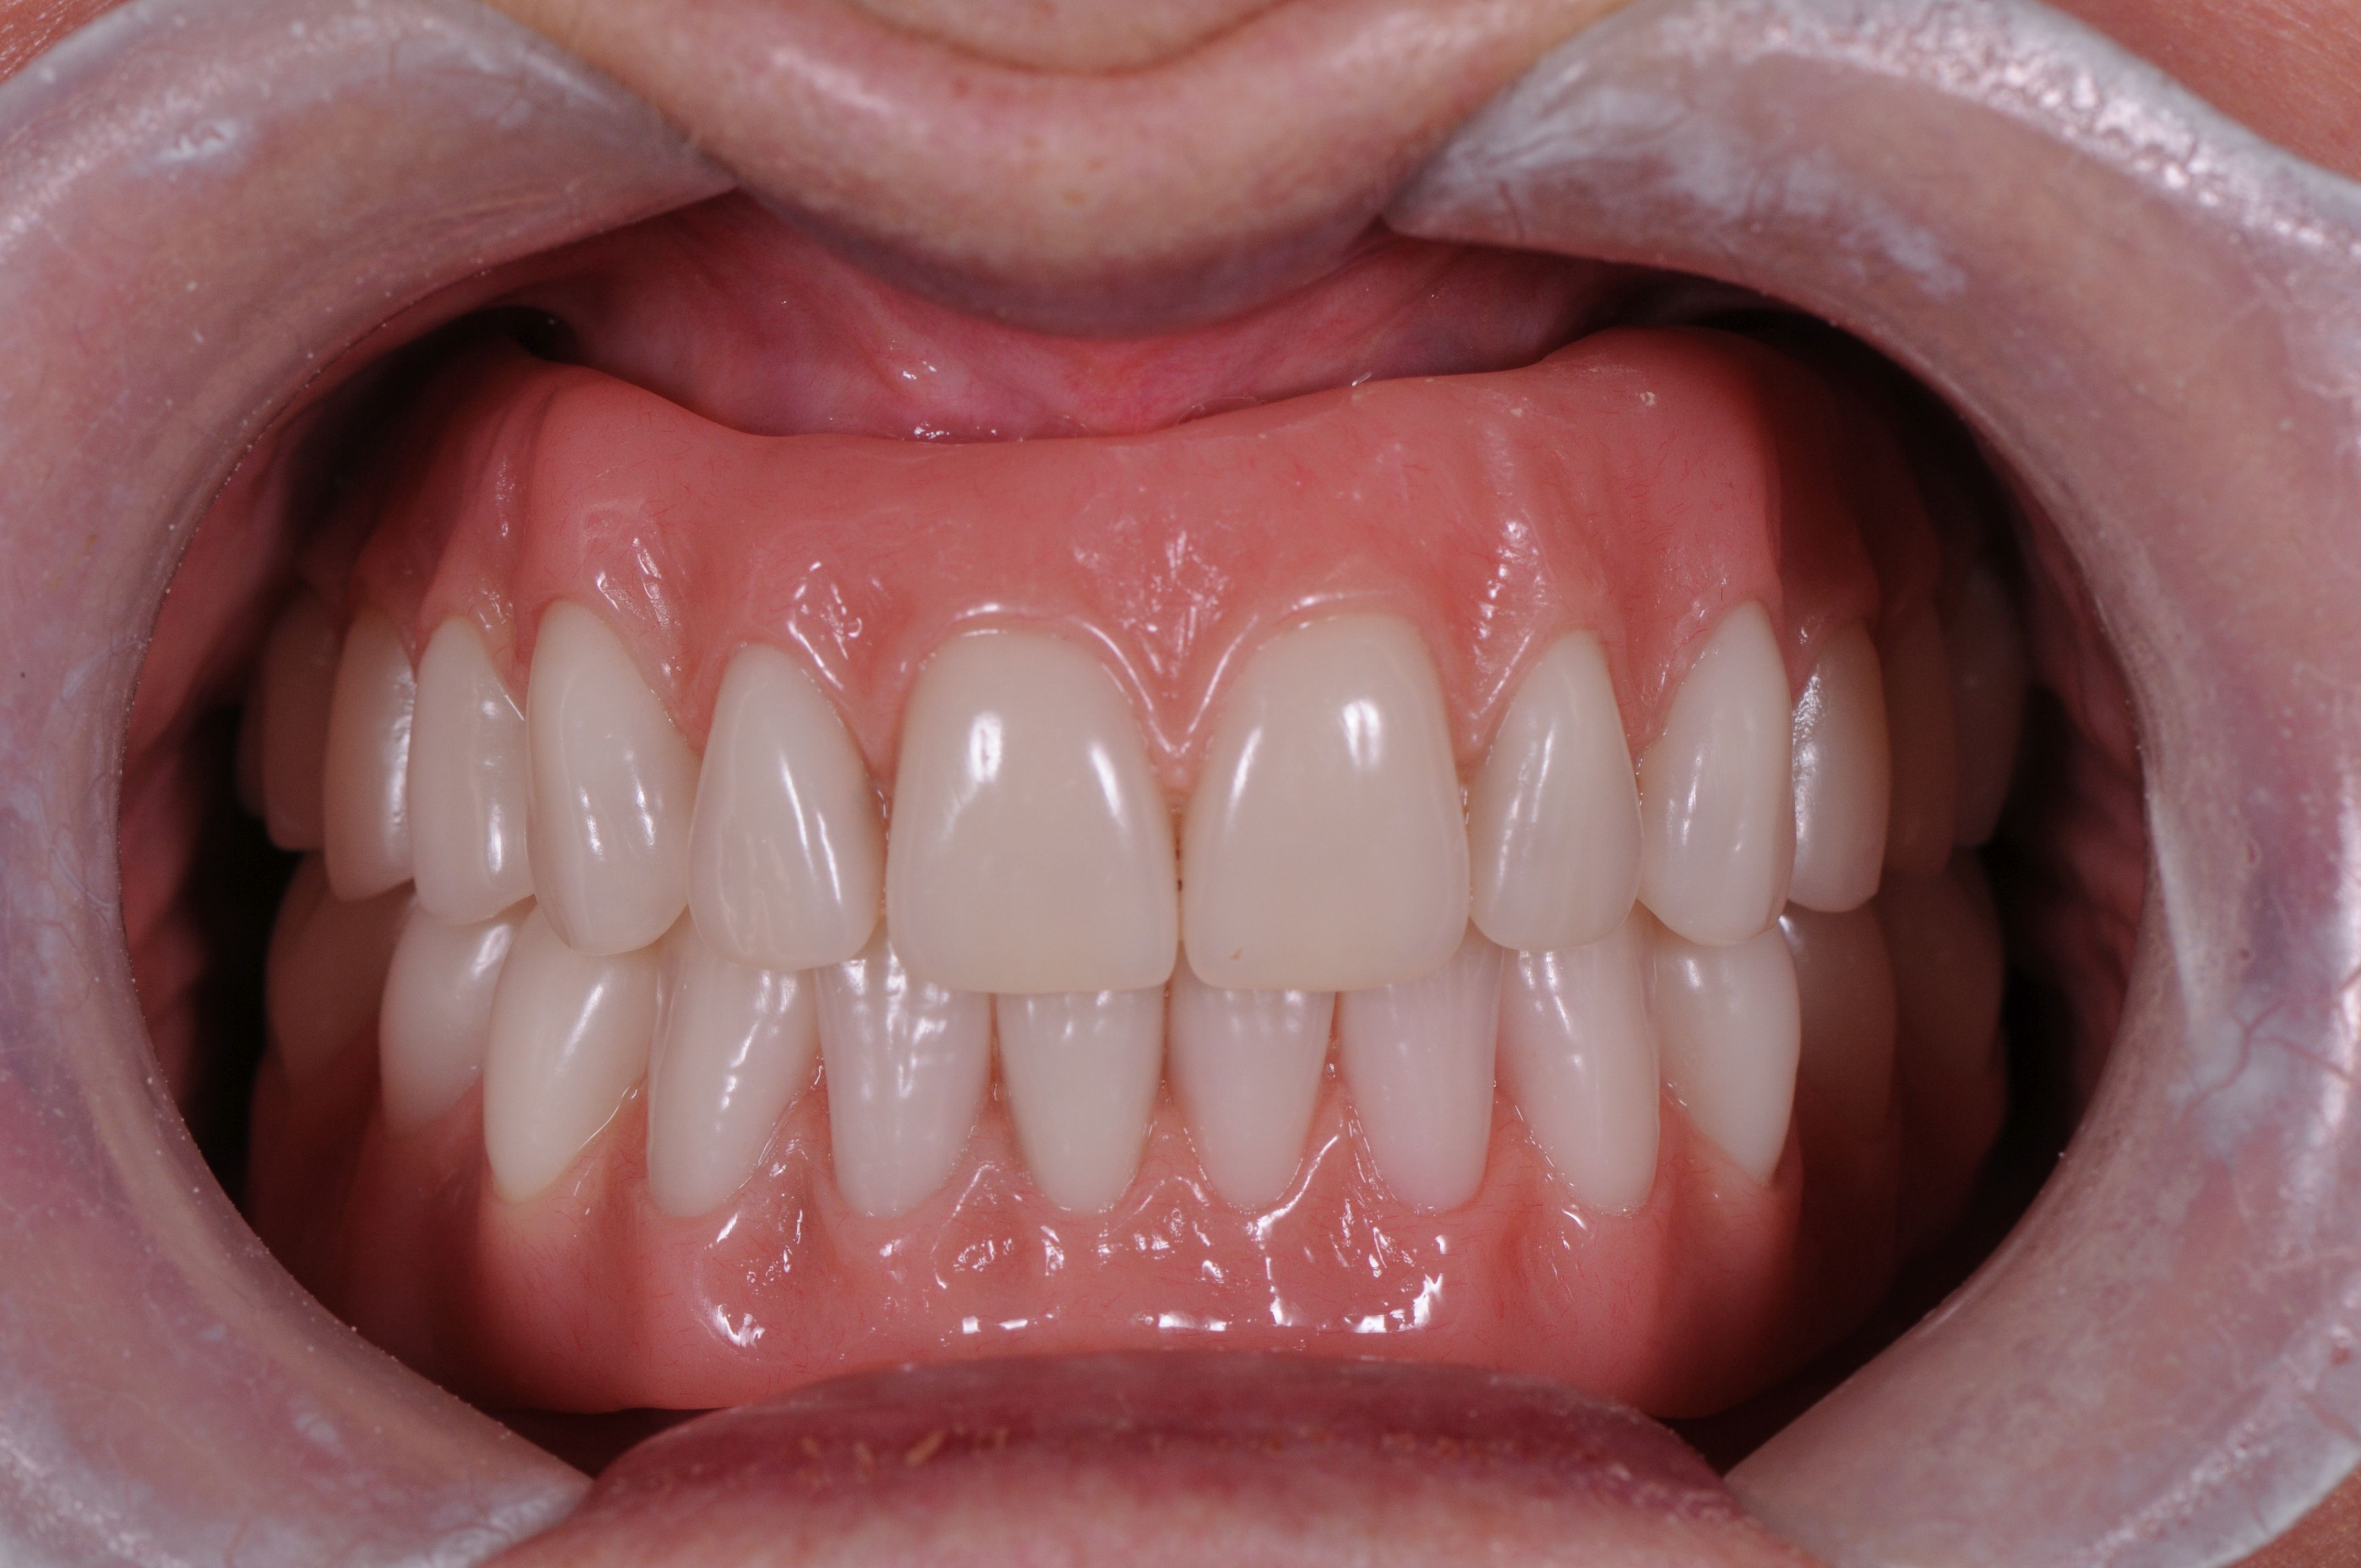

This photo shows the upper bridge. It also was made to fit over four small conical attachments on four implants. As it can be removed periodically by the patient, cleaning the bridge or cleaning the gum and implants becomes very simple.

The lower bridge was similar in design. The bridges can be quite fine, or they can be thicker with some pink added to them, if the person is needing some additional lip support.